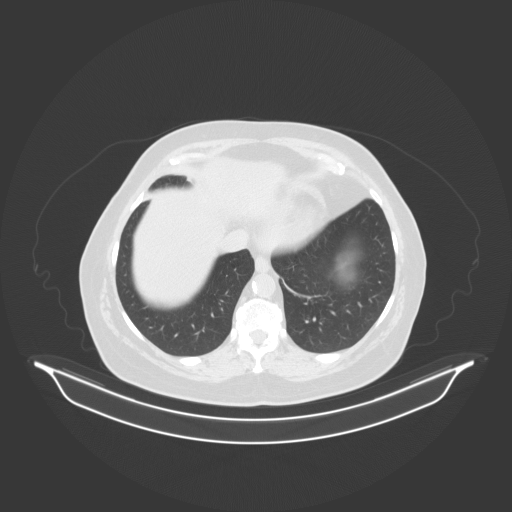

Original VENOUS CT scan

No window - Raw intensity values

Lung window (WL -600, WW 1500 β†’ Low βˆ’1350, High +150)

Mediastinum window (WL 40, WW 400 β†’ Low βˆ’160, High +240)